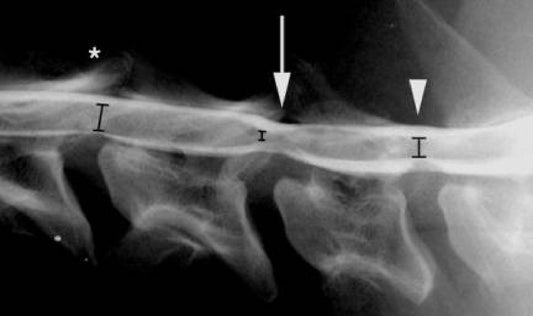

ΣΥΝΔΡΟΜΟ WOBBLER ΑΥΧΕΝΙΚΗ ΣΠΟΝΔΥΛΟΜΥΕΛΟΠΑΘΕΙΑ ΣΚΥΛΟΥ

Το σύνδρομο Wobbler σε σκύλους είναι επίσης γνωστό ως «αυχενική σπονδυλομυελοπάθεια σκύλου»,...